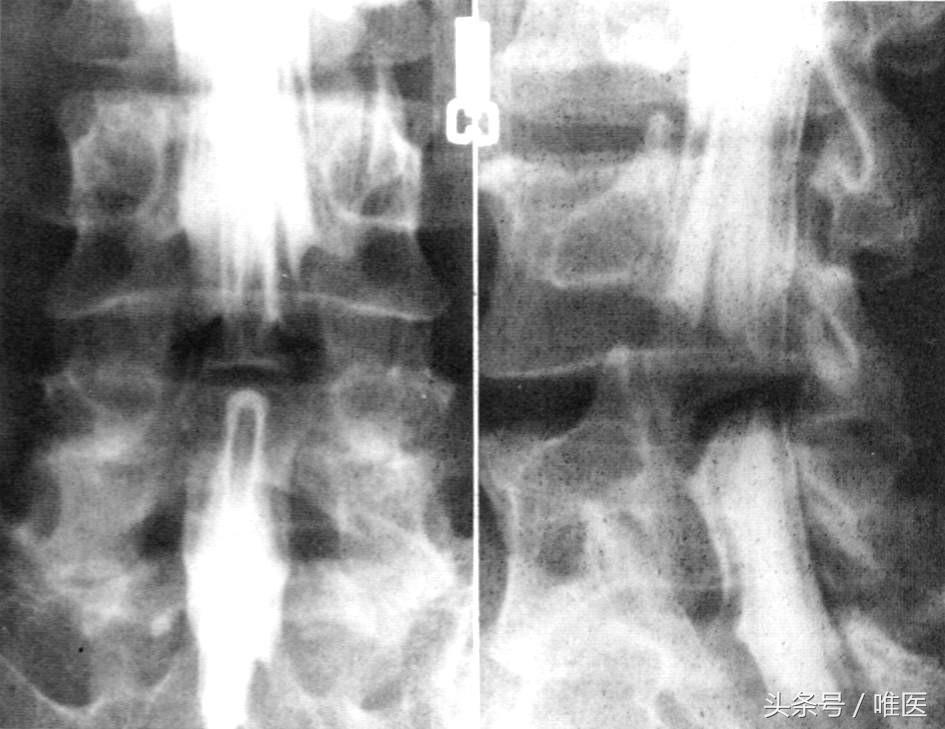

1.X线检查

在CT和MRI尚未问世或普及应用前,摄取腰椎正位片与侧位X线片进行椎管径的测量,是评估腰椎椎管狭窄的主要手段。其具体方法为:通过正位片进行椎管横径(双侧椎弓根内缘的间距)的测量和侧位片椎管矢状径(椎体后缘至椎板与棘突交界处的距离)的测量。以往认为横径小于18mm,矢状径小于13mm提示存在有椎管狭窄。

现在X线检查更多的是作为诊断的辅助检查,X线上可以观察脊柱曲度的改变,椎间高度的变化,有无椎体边缘骨赘,关节突关节形态,有无椎体不稳或滑脱。

2.椎管造影

腰椎管狭窄者椎管造影均有不同程度的造影剂充盈缺损。完全梗阻断处常呈幕帘状、笔尖状,弹头状样充盈缺损。完全梗阻断处常呈点滴状通过,其结果呈葫芦状、哑铃状或灯笼状等。椎管造影的一个最大的优点是可以让患者在后伸、前屈等不同体位下进行拍片,从而能显示不同体位的动态变化,为临床诊断与治疗提供重要的依据。这是其他检察方法所难以发现的。但椎管造影为有创性检查,患者不易接受,且侧隐窝病变不能清晰显示,不能显示椎管横断面骨和神经根形态。目前绝大多数腰椎管狭窄症可以通过CT或MRI准确的诊断,椎管造影检查在临床应用已经很少。